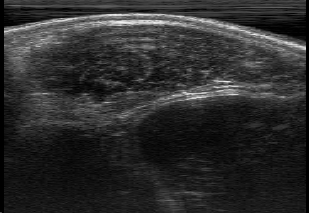

Rib Eye Area (REA). This image dataset consists of ultrasound images of the Longissimus dorsi muscle between the 11th and 13th ribs of cattle. The goal is to automatically calculate the rib eye area (REA), an important region for decision making during cattle breeding. The main challenge is the uncertainty in the REA annotation, since the image is noisy and even experts have difficulty in delimiting the borders of this region. Fig. 3 presents examples of images and the annotation made by a specialist. We can observe that some borders are absent and depend on the subjectivity and knowledge of the annotator. To evaluate the segmentation methods, 76 images with resolution were obtained and labeled by an expert. Due to the number of images, the division of the images in training and testing followed 5-fold cross-validation.

REA dataset. This image dataset has high uncertainty during labeling due to noise from the ultrasound image. In some cases, the border of REA is not completely visible and must be estimated by the specialist. Therefore, the proposed approach becomes essential to obtain accurate segmentation at the edges. The segmentation examples in Fig. 6 show that the baseline was not able to define the REA correctly due to the uncertainty of the labeling. On the other hand, the proposed approach presents results close to the specialist in regions that the border needs to be estimated.